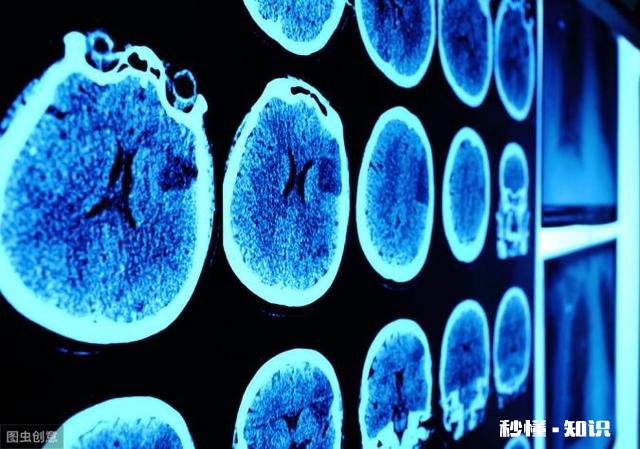

个别轻度脑出血病人临床症状轻,与脑梗死相似,两者难以鉴别 。而大面积脑梗死病人,出现颅内压增高,意识障碍时,也酷似脑出血,临床上不好区分 。要力争尽早做CT扫描检查 。

文章插图

脑出血的CT表现为高密度阴影,而脑梗死表现为低密度阴影,两者截然不同 。